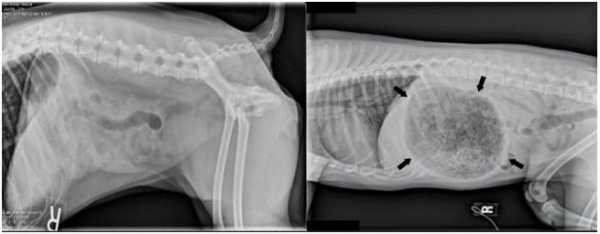

- Keep glues out of reach. Some glues, such as Gorilla Glue®, expand greatly once ingested and require surgical removal. Just one ounce of glue may expand to the size of a basketball, as illustrated in the side-by-side image below. To avoid this situation, be sure to keep glues out of the reach of pets!